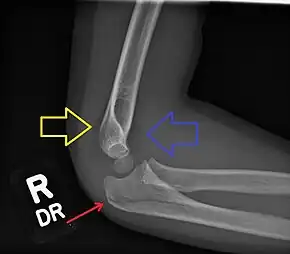

Fractured elbow in a child (ulnar shaft) with joint effusion of elbow